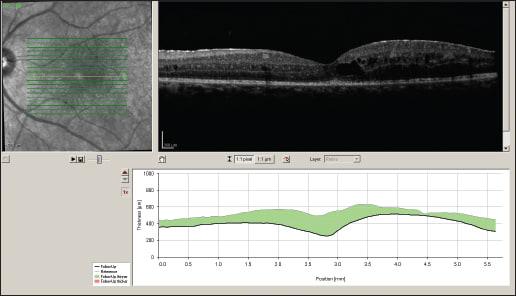

We diagnosed Birdshot chorioretinitis, and started the patient on an anti-inflammatory regimen that included 60 mg of oral prednisone daily as well as periocular injection of triamcinolone acetonide OU. However, there was no significant improvement in visual acuity or CME (Figure 2).

Figure 2. Left eye (top image) and right eye (bottom image) six weeks after starting systemic and periocular therapy.